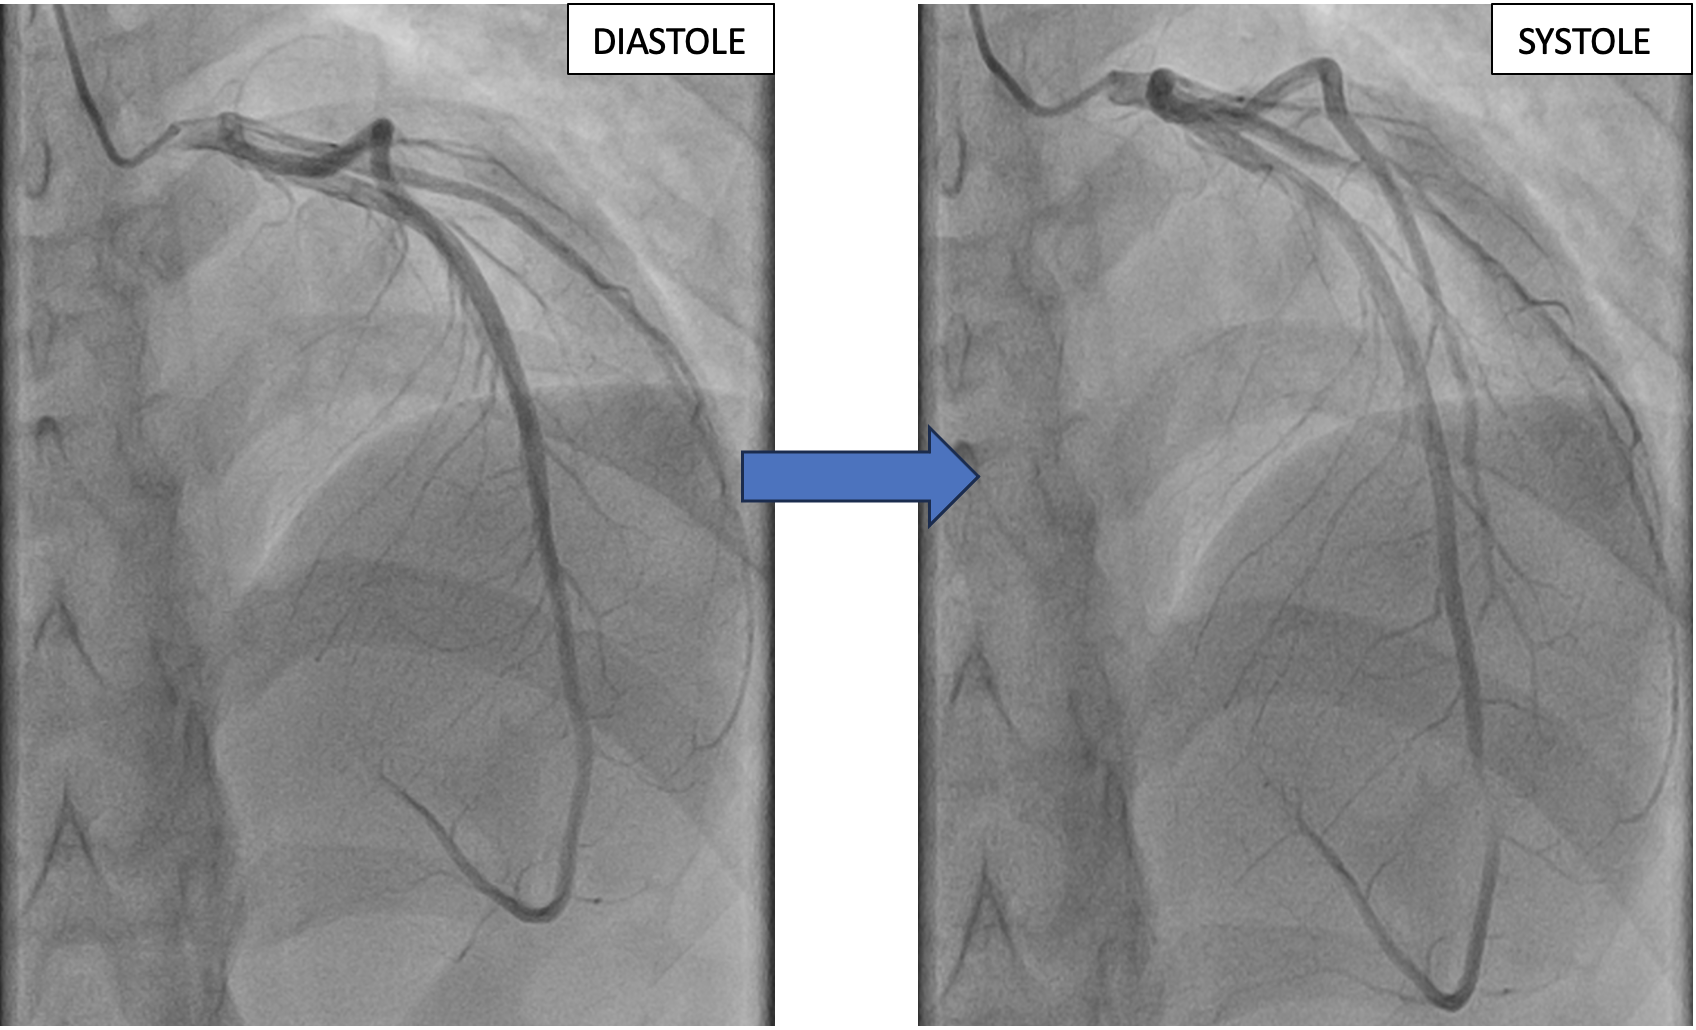

Image of the Week - 19 February 2025

Doctor Nassima EL KARROUMI

Mrs Kenza Alami

Professor Najat Mouine